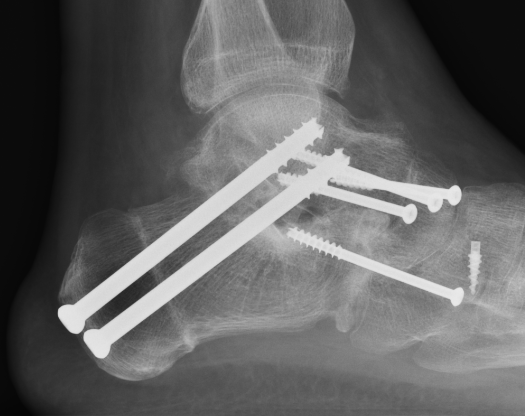

Triple Arthrodesis

Aim

Realign hindfoot with plantigrade foot

Technique

Lengthen tendoachilles - gastrocnemius recession / release

Lateral approach to subtalar and CCJ / medial approach to TNJ

Remove articular cartilage and prepare joints for fusion

Reduce joints

- Grice maneuver - laminar spreader between anterior process of calcaneus and talus

- check subtalar joint alignment - slight valgus / not neutral or varus

- may need to add medial slide calcaneal osteotomy

Fuse TNJ first to align STJ

Fuse STJ

- may need large lateral bone wedge

- may have issues with lateral skin closure

Fixation - screws / plates / staples

+/- medial osteotomy to allow medial metatarsal weight bearing

- Cotton osteotomy (cuneiform) / first metatarsal osteotomy